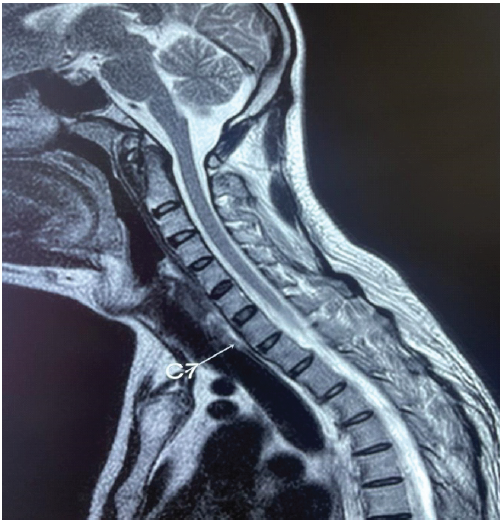

An Unusual Case of Early-onset Ankylosing Spondylitis with Predominant Cervical Spine Involvement

S Venkatesh Kumar , Jalpesh Sureshbhai Kapuriya , Rupali Dnyandeo Solankey , K G Sathyendra , Rohini Venkatesh , Arun Pandian